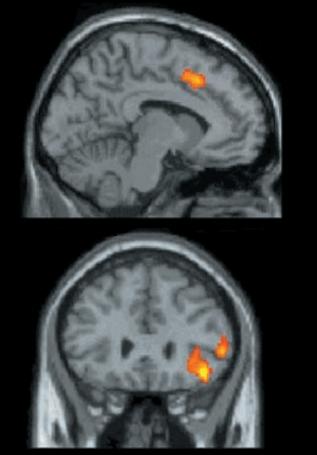

It transpired that there really exists a statistically relevant overlap of areas which activate during both types of pain. Those are namely the anterior cingulate cortex and the right ventral prefrontal cortex.

The former area is considered to be the “alarm system” which activates when something is not right – for instance, when experiencing pain. It activated in this research when the individual was excluded from the game, i.e. he or she was experiencing social pain.

The latter area activates (among others) during inhibition and coping with physical pain. In this research, however, it activated when the player re-joined the game and was passed a ball. This research brought the information that experiencing physical and social pain has the same base.

Fig. 2. The upper image shows the activation in the area of anterior cingulate cortex, the lower in the right ventral prefrontal cortex. Adapted and edited from Eisenberger (2003)